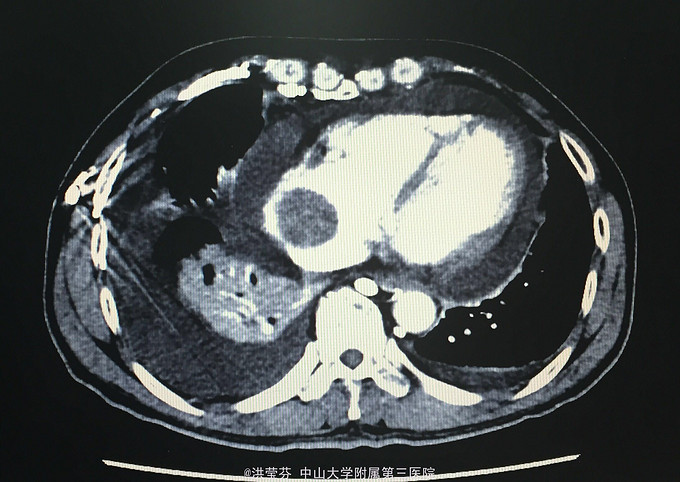

查体:KPS 60分,BSA 1.83m2,T 38.5℃,全身浅表淋巴结未触及明显肿大,胸壁可见浅表静脉曲张,呼吸急促,左下肺、右中下肺呼吸音明显减弱,其余肺野呼吸音促,可闻及少许实性啰音,心率110bpm,律齐,腹软,全腹无压痛、反跳痛,未扪及明显包块,肝脾肋下未触及,移动性浊音(——),肠鸣音正常,4次/分,双下肢无凹陷性水肿。 辅助检查:血常规无特殊,生化转氨酶稍升高,低钠低氯,CRP 227.9mg/L,凝血四项:Fib 8.14g/L。复查胸部CT提示:1.胸腺癌并纵膈淋巴结及双肺多发转移瘤,右心房、上腔静脉受侵并癌栓形成,病变较前进展。2.双肺炎症,以右肺为著。3.双侧胸腔及心包积液。上腹部CT提示:1.下腔静脉早显并肝表面多发侧支形成,考虑右心流出道阻塞所致;腹壁静脉曲张。头颅MR提示右侧颞叶强化灶,结合病史,考虑转移瘤,伴瘤灶少量出血可能,瘤周脑水肿。